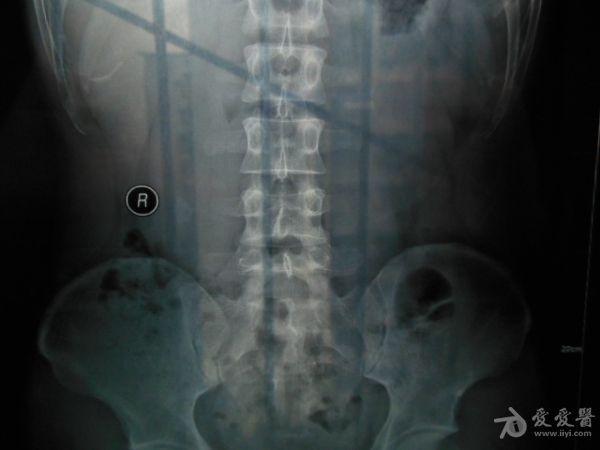

请老师看看这个腰椎和盆骨的平片有无问题

摔了一跤右臀着地,同时闪到腰,查出有椎间盘突出,目前是右臀麻木,整个右腿酸胀沉重。肌力正常走路正常,坐不到5分钟右腿就酸胀难忍。明显觉得左右**感觉不一样,右边软得多,

自觉下腰和盆骨感觉别捏,有歪斜感,扭腰时觉得舒服。腰4右侧一下有异物感。今天照了个腰椎正侧位和盆骨的正位平片,医生说没什么问题,拿来请各位老师看看腰椎和盆骨有没有错位,旋转,不等高等情况,再次感谢。

照该片看应该是骨盆旋移

这种症状拍平片没有什么意义,选择MRI或者CT吧

看片子没发现什么大的问题,没有骨折,没有增生。腰椎间盘突出做核磁共振最清楚。